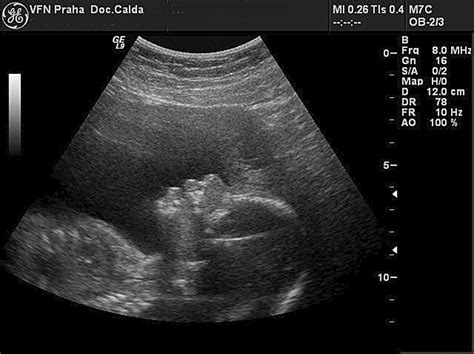

V roku 2019 sa medzi spontánne potraty zaradili aj takzvané zamĺknuté potraty. Je to stav definovaný ultrazvukovým nálezom, pri ktorom sa preukáže zastavenie vývoja plodu s nemožnosťou dokázať akciu srdca, pričom plod ešte nebol vypudený z dutiny maternice, ale ostáva v nej zadržaný.

V diagnóze a ďalšej prognóze je dôležité skoré gynekologické vyšetrenie, sonografia, stanovenie hormonálnych hladín (stanovenie HCG v moči, sére a stanovenie sérového progesterónu).

Poskytovateľ starostlivosti o tehotenstvo môže vykonať ultrazvukový test na potvrdenie potratu. Tieto testy kontrolujú srdcový tep plodu alebo prítomnosť žĺtkového vaku. Na kontrolu potratu sa odporúča krvný test, pretože test meria ľudský choriový gonadotropín (hCG), hormón vytvorený placentou. Nízka hladina hormónov naznačuje potrat.